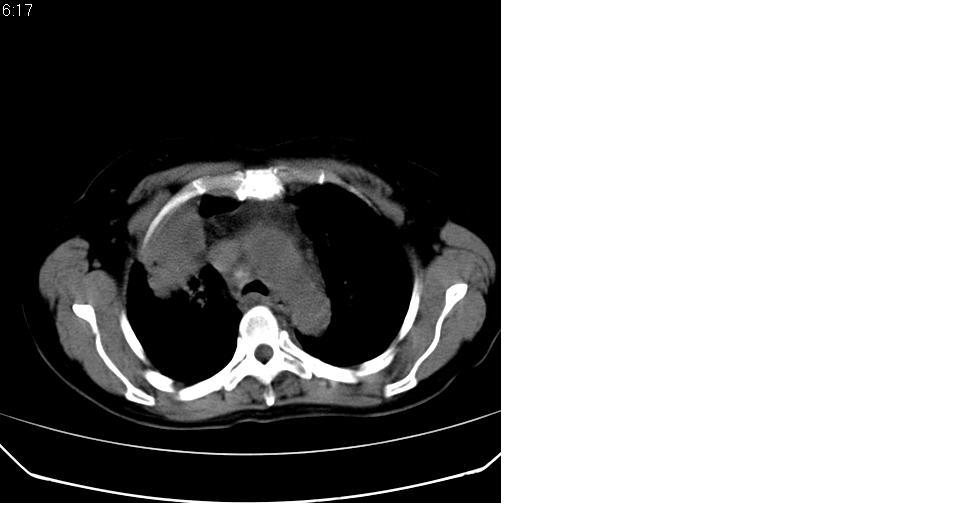

标题: CT16839:胸部CT平扫

女 50岁,在其他医院确诊肺癌.

肺癌并肺及纵隔转移

支持 右肺上叶肺癌并两肺及纵隔转移。